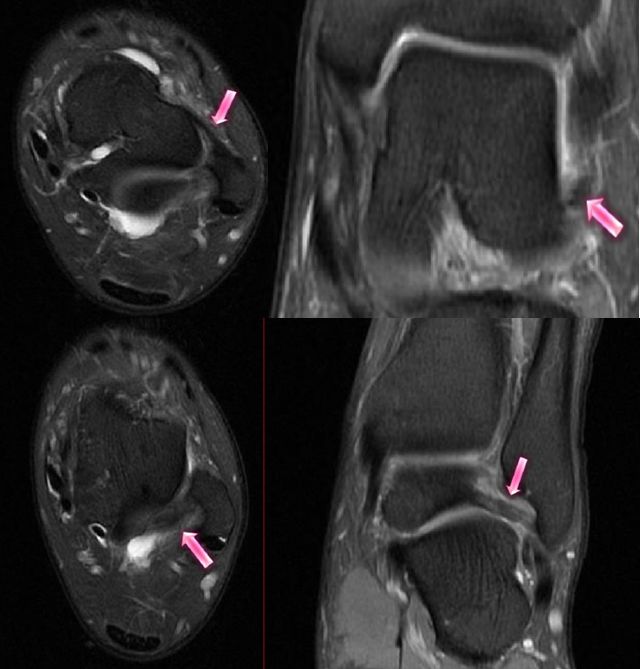

二、骨软骨损伤

好发于距骨前外侧、后内侧,尤其是后内侧,与内翻损伤相关。

MRI表现为软骨下骨质内斑片状或囊状T1WI低信号、STRI高信号影,伴或不伴小骨软骨碎片的分离、移位。